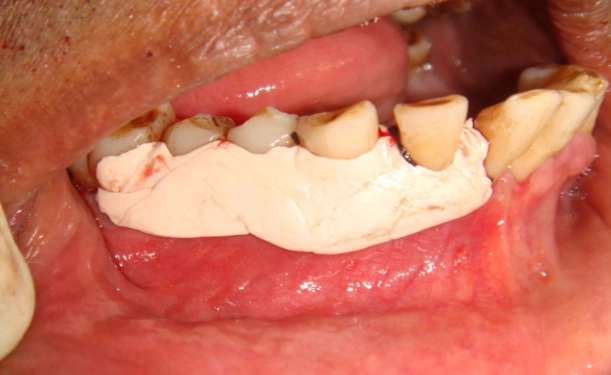

The surgery (toriectomy or tori reduction) is usually performed by an oral surgeon. Under local anesthesia (often with sedation if you're anxious or if it's a large area), the surgeon makes a careful incision over the tori, peels back the gum tissue to expose the bone, and then uses a combination of specialized burs and chisels to remove the excess bone. The goal is to create a smooth contour. The gum is then stitched back into place with dissolvable sutures.